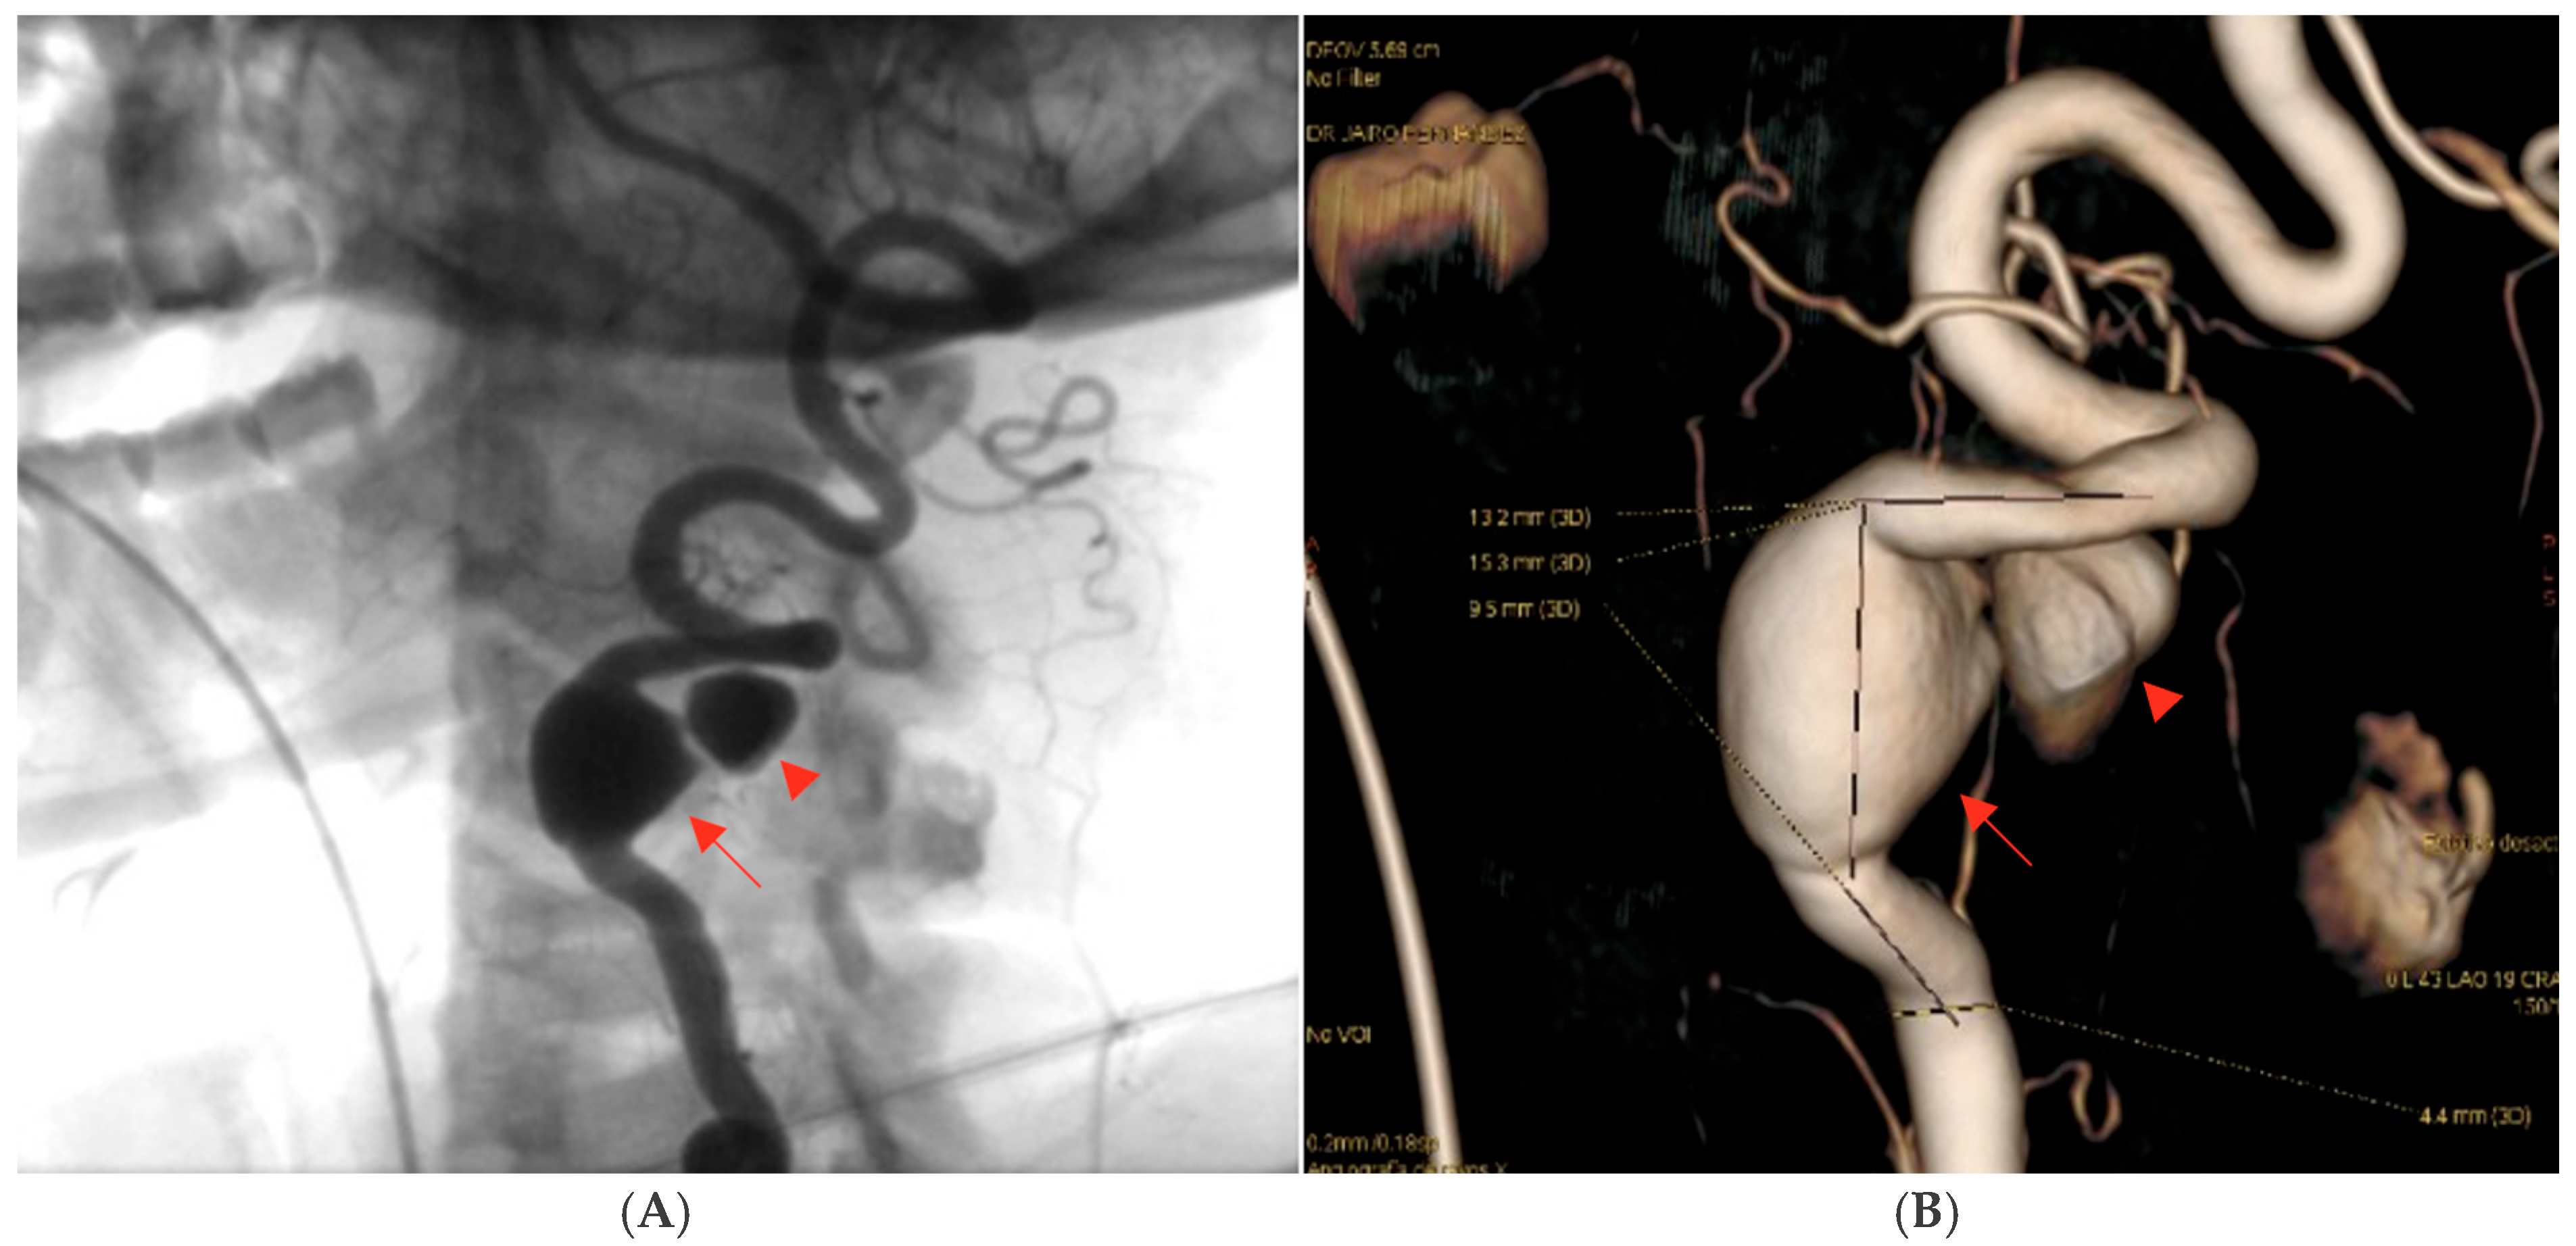

Digital subtraction angiography (DSA) confirmed the presence of a dissecting fusiform aneurysm of the left vertebral artery at the V1–V2 junction, associated with a contained pseudoaneurysm. The true aneurysmal dilation measured 18 × 15 mm, while the pseudoaneurysm was not quantified separately. The V1 (pre-foraminal), V3 (extradural), V4 (intracranial) segments, and the basilar artery were normal. A right P1 segment agenesis with a fetal-type posterior communicating artery was also observed (Figure 3). The apparent discrepancy in aneurysm size between CTA and DSA can be explained by the different imaging principles: CTA captured both the intraluminal aneurysmal dilation and the adjacent perivascular hematoma/pseudoaneurysmal component, whereas DSA more accurately reflected the true intraluminal dimensions of the dissecting aneurysm.

Figure 3. Digital subtraction angiography (DSA) of the left vertebral artery demonstrating a dissecting fusiform aneurysm at the V1–V2 junction with an associated contained pseudoaneurysm. The fusiform aneurysmal dilation measured approximately 18 × 15 mm; the pseudoaneurysm was not quantified separately. The procedure was performed after intra-arterial administration of 10–15 mL of non-ionic iodinated contrast medium (Iohexol, Omnipaque® 300 mg I/mL) per injection, delivered at an injection rate of approximately 4–6 mL/s, with high temporal resolution acquisitions (2–3 frames/s) during the arterial phase: (A) Oblique projection after intra-arterial contrast administration showing the dissecting fusiform aneurysm. (B) Three-dimensional reconstruction confirming the aneurysmal morphology and vessel anatomy. The aneurysm is indicated by red arrows, while the mural defect is highlighted by a red arrowhead. The remaining vertebrobasilar segments were unremarkable. Source: patient’s medical record, published with prior authorization.